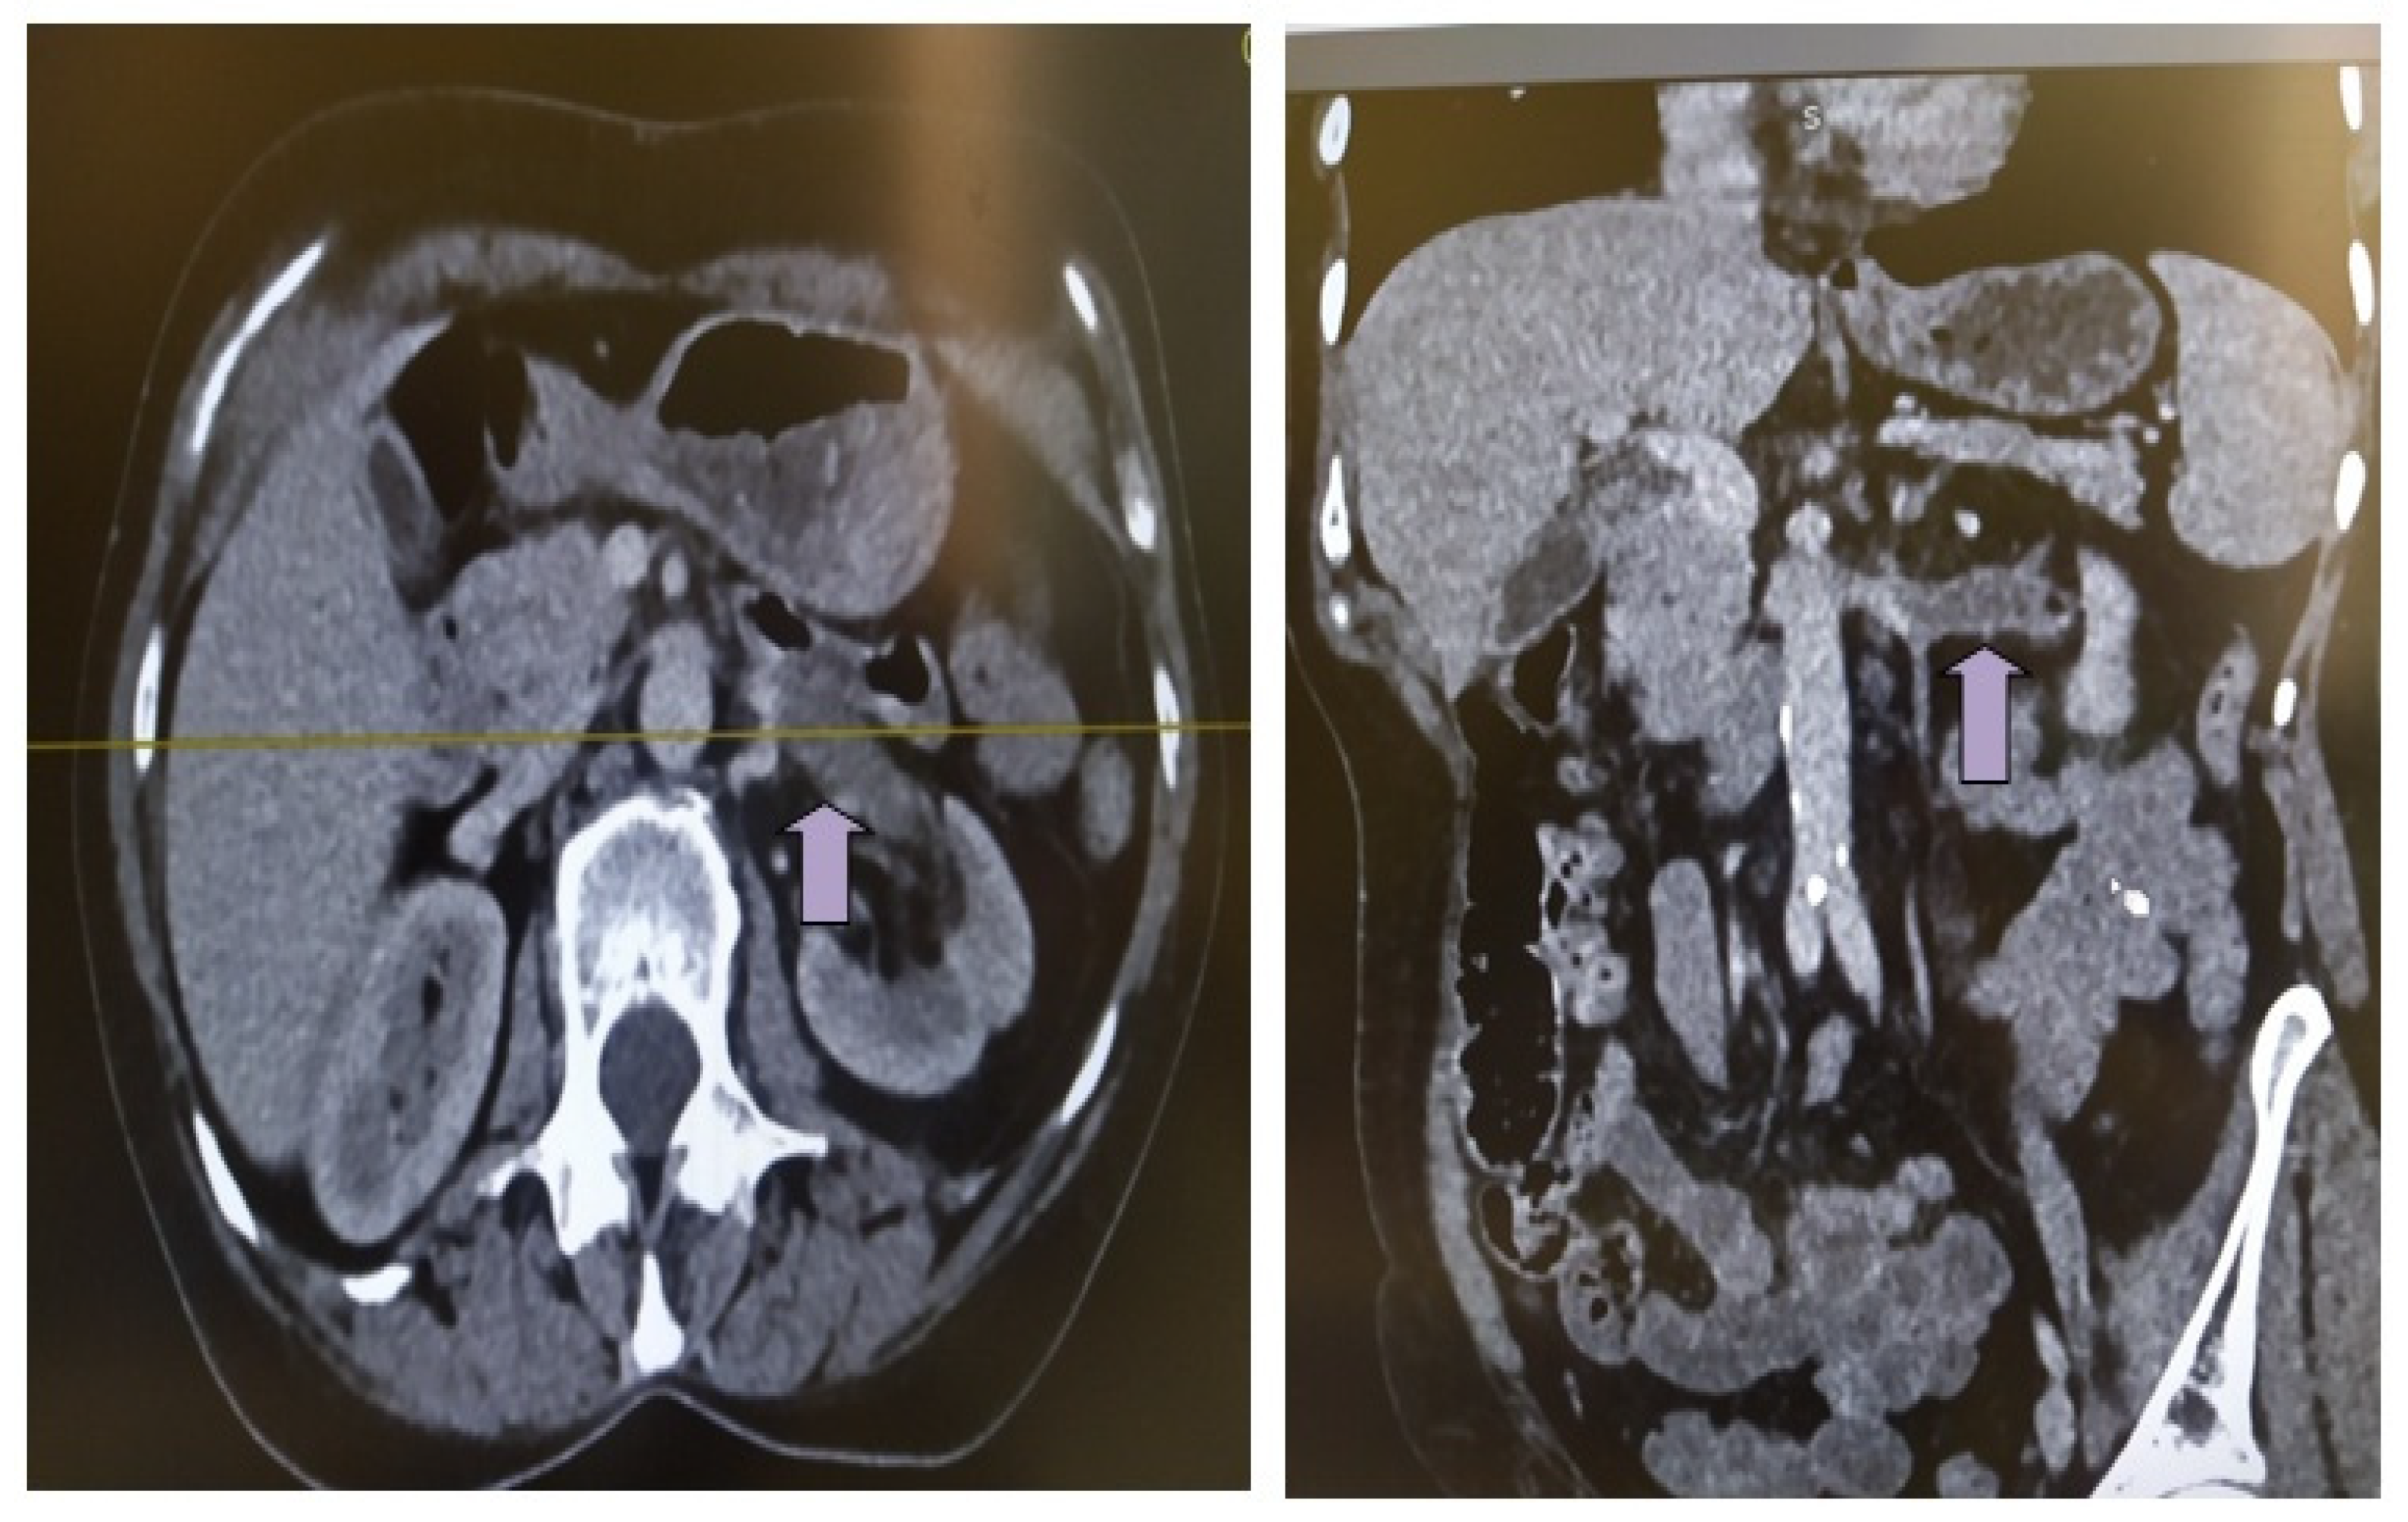

The presenting symptoms of acute renal vein thrombosis (rvt) can often be confused with. a rare case of a 35 years old woman presented with renal arcuate vein thrombosis (ravt) and acute kidney injury. here, we describe a case of acute onset flank pain caused by unilateral renal vein thrombosis (rvt) in a previously healthy patient. renal vein thrombosis (rvt), the presence of thrombus in the major renal veins or its tributaries, is a rare clinical entity.

Case Report On Renal Vein Thrombosis here, we describe a case of acute onset flank pain caused by unilateral renal vein thrombosis (rvt) in a previously healthy patient. a rare case of a 35 years old woman presented with renal arcuate vein thrombosis (ravt) and acute kidney injury. here, we describe a case of acute onset flank pain caused by unilateral renal vein thrombosis (rvt) in a previously healthy patient. The presenting symptoms of acute renal vein thrombosis (rvt) can often be confused with. renal vein thrombosis (rvt), the presence of thrombus in the major renal veins or its tributaries, is a rare clinical entity.